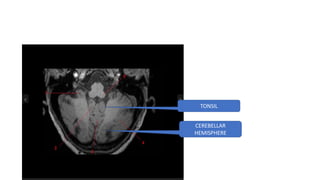

CEREBELLUM

TONSIL

CEREBELLAR

HEMISPHERE

VERMIS

MIDDLE CEREBELLAR PEDUNCLE

SUPERI0R CEREBELLAR PEDUNCLE -MIDBRAIN LEVEL

HORRIZONTAL FISSURE

SUPERIOR CEREBELLAR PEDUNCLE -MIDBRAIN LEVEL

MIDDLE CEREBELLAR PEDUNCLE AT PONS